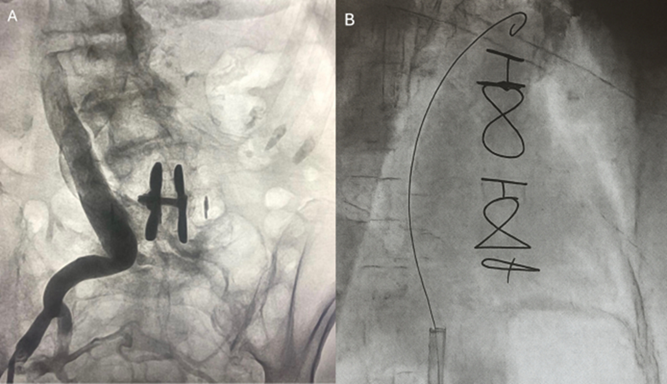

This single-center, retrospective case series included patients who underwent AVEIR implantation via the RIJ vein between 2023 and 2025. The RIJ approach was selected when the femoral route was not feasible because of venous tortuosity, the presence of IVC filter, or difficult venous anatomy that prevented safe advancement of the delivery system (Figure 1).

All procedures were performed under fluoroscopic guidance. Venous access was obtained in the RIJ vein under ultrasound guidance. A single Perclose ProGlide suture (Abbott) was deployed and secured with hemostats using the preclose technique. Serial dilatation allowed placement of the AVEIR delivery sheath. In cases of AVEIR VR, the sheath was advanced into the right atrium and carefully manipulated across the tricuspid valve into the right ventricle. Device deployment was performed at the right ventricular septum, and stability was confirmed with the standard tug test. Electrical performance was assessed by measuring sensing and capture thresholds, and final device release occurred only after implant criteria were satisfied (Figure 2). The delivery sheath was subsequently removed, and hemostasis was achieved with ProGlide closure in all patients.